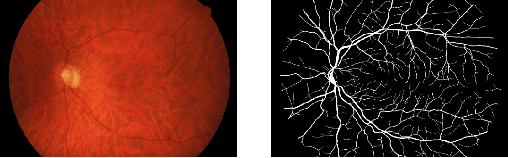

Deep learning models have shown promising results in a wide range of computer vision applications across various domains. The success of deep learning methods relies heavily on the availability of a large amount of data. Deep neural networks are prone to overfitting when data is scarce. This problem becomes even more severe for neural network with classification head with access to only a few data points. However, acquiring large-scale datasets is very challenging, laborious, or even infeasible in some domains. Hence, developing classifiers that are able to perform well in small data regimes is crucial for applications with limited data. This paper presents CvS, a cost-effective classifier for small datasets that derives the classification labels from predicting the segmentation maps. We employ the label propagation method to achieve a fully segmented dataset with only a handful of manually segmented data. We evaluate the effectiveness of our framework on diverse problems showing that CvS is able to achieve much higher classification results compared to previous methods when given only a handful of examples.